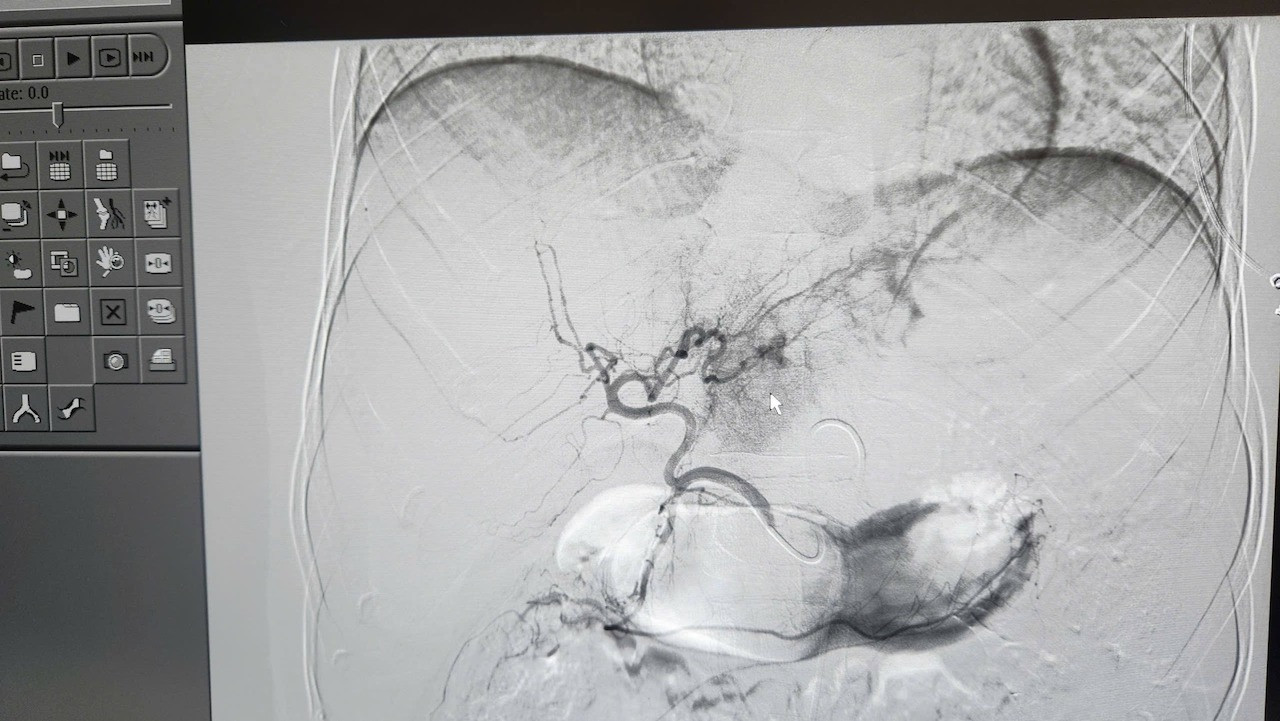

Ca can thiệp do ê-kíp can thiệp mạch của Khoa Chẩn đoán hình ảnh thực hiện với sự chỉ đạo trực tiếp của bác sĩ CKII Ngô Vĩnh Hoài, Phó Trưởng khoa. Nhờ hệ thống chụp mạch số hóa xóa nền (DSA), các bác sĩ đã xác định chính xác vị trí tổn thương và kiểm soát hoàn toàn điểm chảy máu.

Các bác sĩ can thiệp. nút mạch cho bệnh nhân. Ảnh: BVCC.

Theo bác sĩ Hoài, đây là kỹ thuật phức tạp, đòi hỏi thao tác chính xác từng milimet nhằm kiểm soát hoàn toàn điểm chảy máu. Phương pháp này giúp cầm máu tức thì, bảo tồn tối đa phần gan lành, đồng thời rút ngắn thời gian hồi phục và hạn chế biến chứng so với phẫu thuật thông thường.